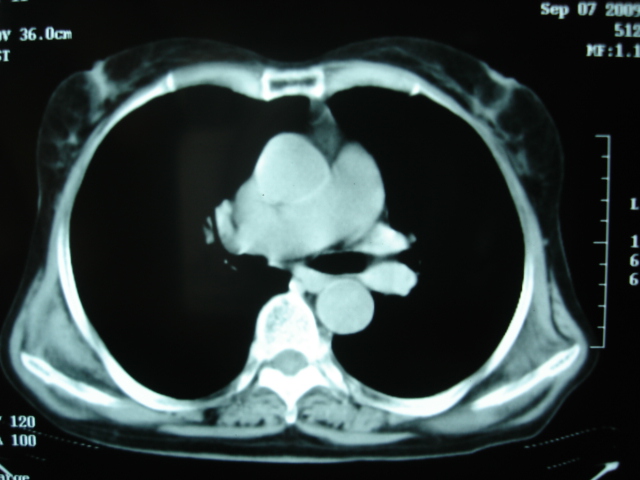

以下是引用卜一在2009-9-7 19:51:00的发言:[br][br] 1 左侧胸内甲状腺占位-多考虑甲状腺腺瘤! 2、左肺门占位-建议增强扫描以便明确性质。 3 慢支并感染! [br]

以下是引用shibing在2009-9-7 20:40:00的发言:[br]左侧胸内甲状腺占位-多考虑甲状腺腺瘤! 2、左肺门占位-建议增强扫描以便明确性质。 3 慢支并感染! [br]